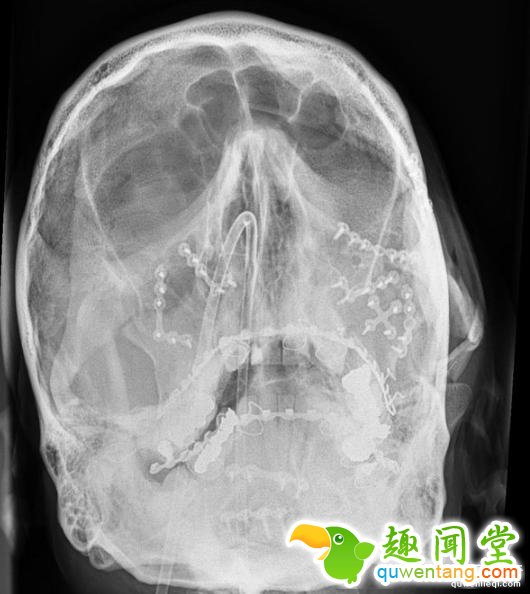

下巴粉碎,左眼眶被撞得往左移了一厘米,鼻梁就更不用说了,当时的x光片记录下这一切,Andy Robinson能活下来已经是一个奇迹。

在医治过程中,医生用了13块金属板和52个螺钉固定头骨,然后是艰难和复杂的脸部修复手术,康复后,Andy Robinson的脸上如果不仔细看,是看不出手术痕迹的,如今,为了以防万一,他不准自己的儿子骑自行车和摩托车。